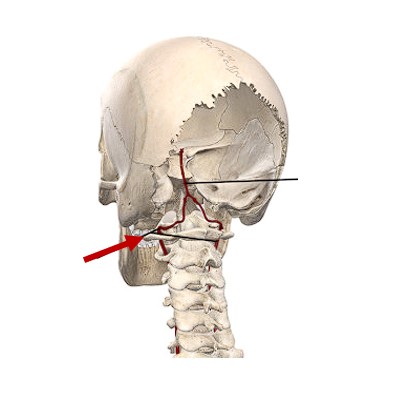

Atlas

Vertebral Artery

(Donor Only)